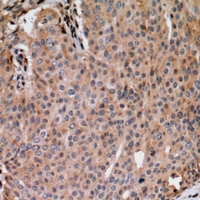

分类: 科研抗体货号: P41227别名: MKI67IP; NOPP34; MKI67 FHA domain-interacting nucleolar phosphoprotein; Nucleolar phosphoprotein Nopp34; Nucleolar protein interacting with the FHA domain of pKI-67; hNIFK应用: WB,IHC,IF反应种属: Human,Mouse,Rat